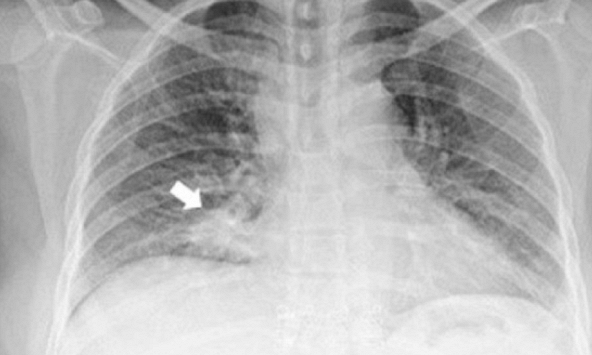

Ngoài nội soi, bác sĩ có thể chỉ định bệnh nhân chụp CT. Bác sĩ chủ yếu dựa vào các hình ảnh để đánh giá tình trạng thương tổn của dạ dày, sự xâm lấn của khối u đến các bộ phận xung quanh. Hơn nữa qua đó có thể đánh giá tình hình của bệnh nếu ung thư bắt đầu di căn đến các bộ phận khác trong cơ thể như: gan, hạch, ổ bụng, ổ phúc mạc…